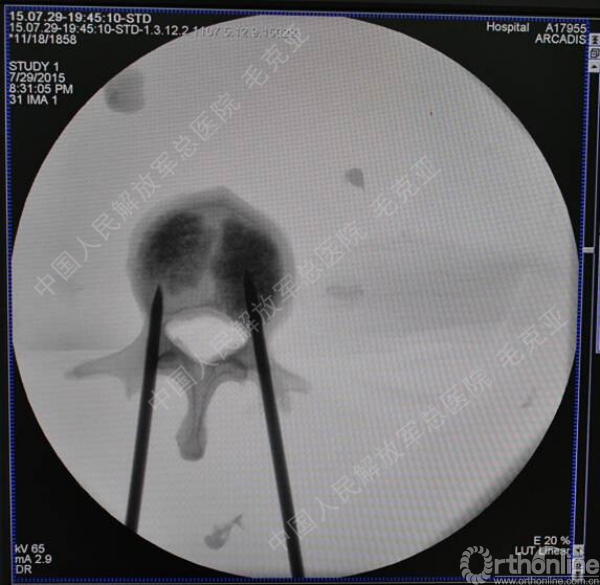

导语:随着社会老龄化的不断加速,骨质疏松性椎体压缩骨折作为一种普遍存在的老年骨科疾病已经成为现今骨科界的一个热点话题。传统的保守疗法治疗效果不佳,而现有的椎体增强技术又具有多种风险和缺陷。针对这种现状,中国人民解放军总医院毛克亚教授提供了一种新的解决方法。